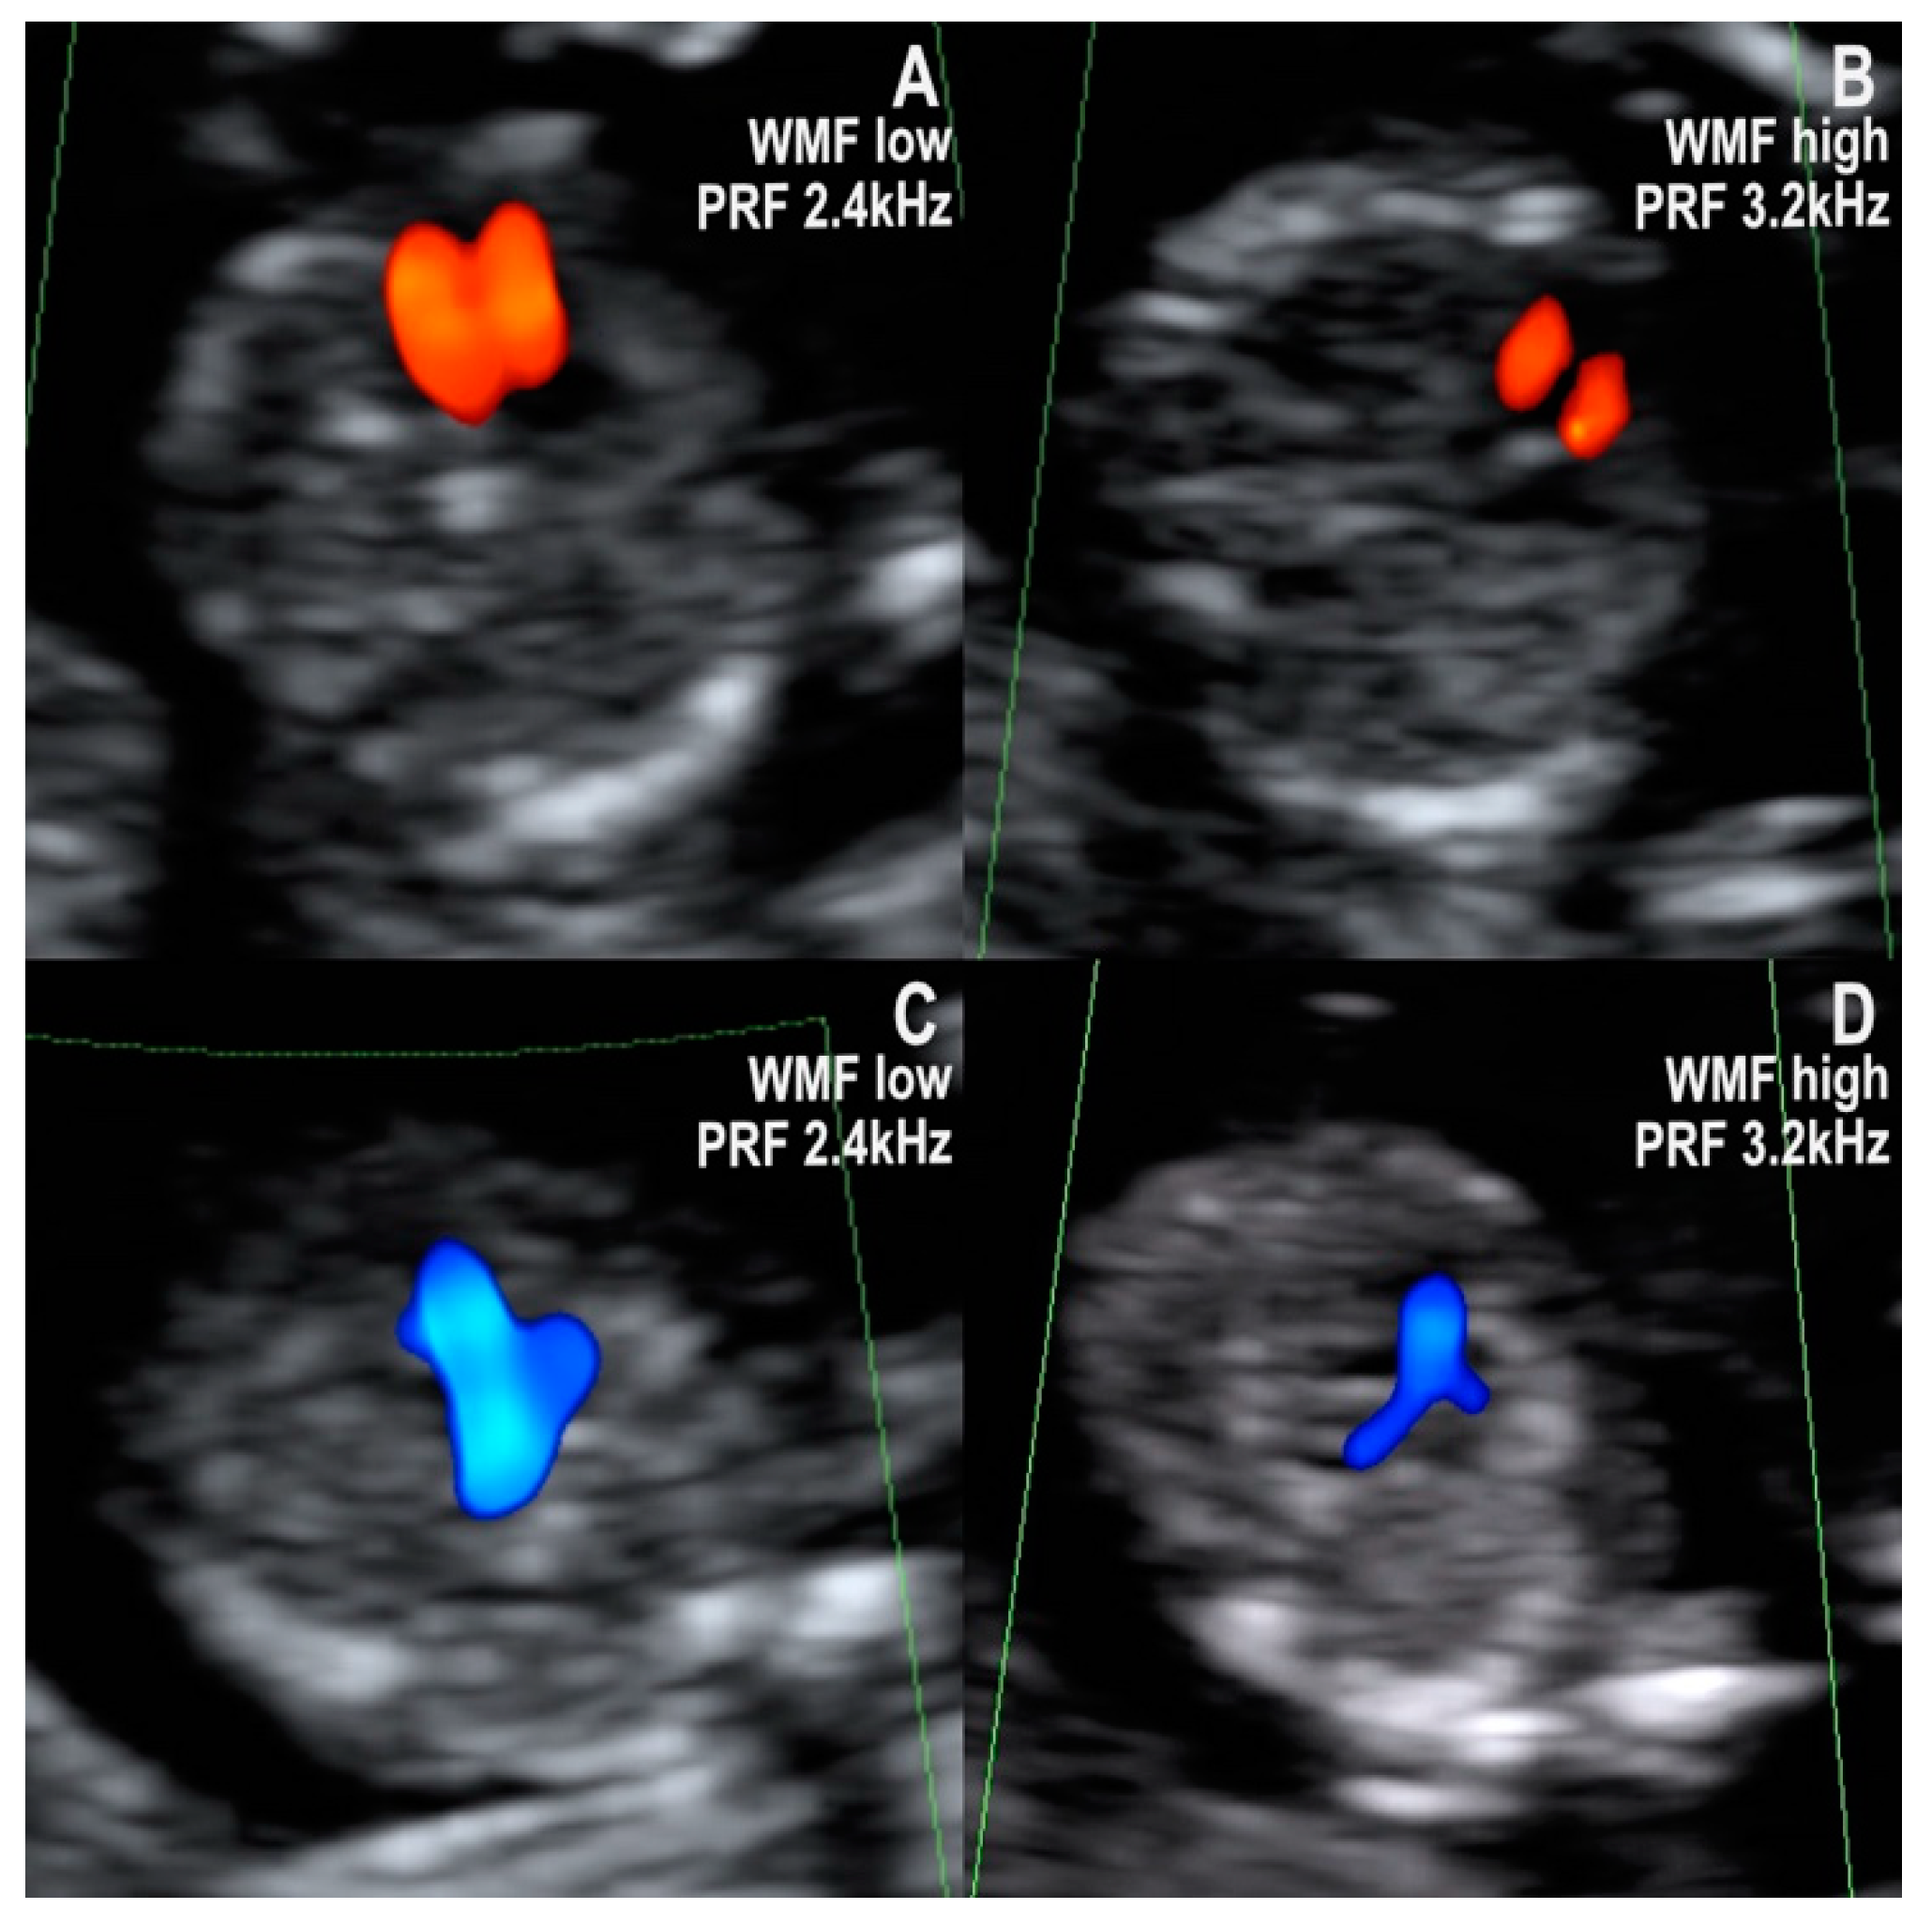

- Filling of only one ventricle and one vessel with a straight course. The six hypoplastic left heart syndrome (HLHS) cases respected this pattern in the first trimester. The pattern was also seen in the one case of a univentricular heart from our collection. In the four-chamber view, only one ventricle (the right one in HLHS) has doppler inflow, while the other one is usually barely visible and has no doppler inflow. Correspondingly, in the three-vessel and trachea view, only one arterial vessel with doppler flow could be seen, namely the pulmonary artery with the ductus arteriosus in cases of a hypoplastic left heart. The prognosis of hypoplastic left heart syndrome, although not entirely predictable, is generally unfavorable, with no possibility of biventricular repair. The parents must be informed accordingly [1,18].